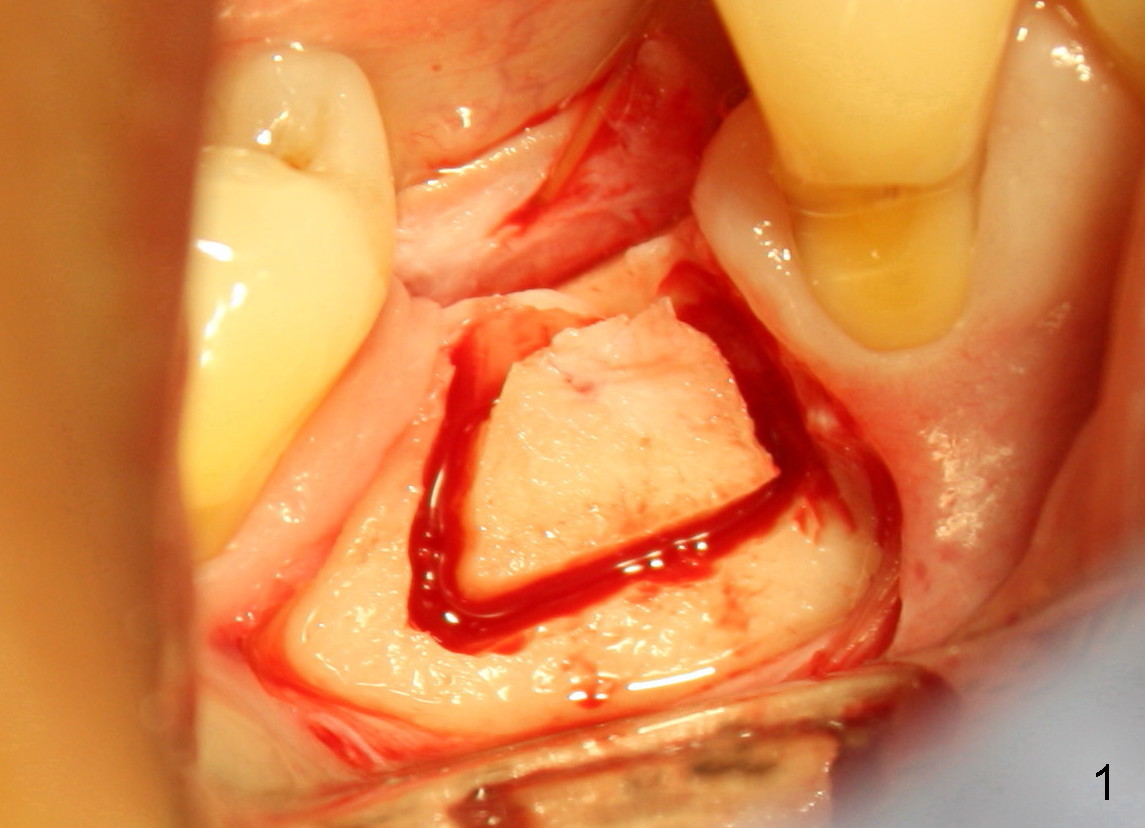

The phobic patient returns 5 weeks after the first surgery. Fig.1, 2 are taken in the first surgery. Fig.2 is used to show that the curved chisel (C) used for the 2nd surgery is wider than the superior bone cut. It appears that the buccal plate does not move when the chisel is applied.